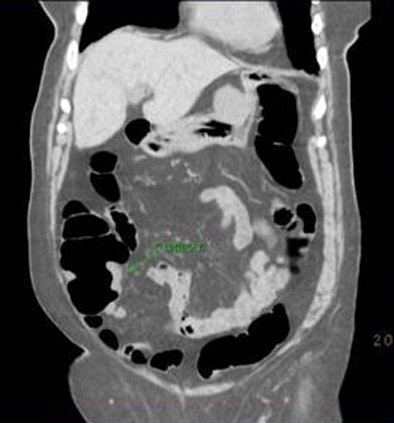

![]() |

| CTC in a 78-year-old woman with incomplete colonoscopy demonstrates cecal carcinoma. All images courtesy of Dr. Hanna Zafar and Dr. Anna Lev-Toaff. |